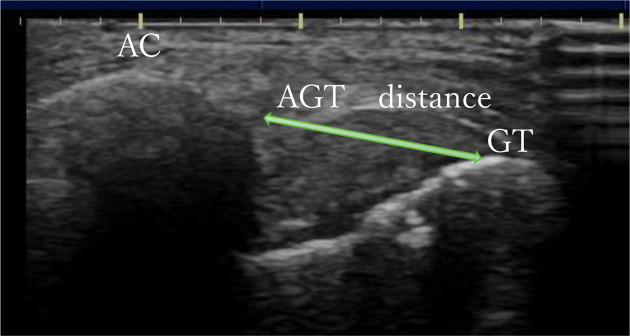

[Purpose] To confirm the reliability and validity of the acromion-greater tuberosity (AGT) distance measured using ultrasound and to investigate its relationship with functional impairments inpatients with stroke. [Participants and Methods] Twenty-four patients with stroke admitted between May and September 2024 were evaluated. Physical function assessments included motor paralysis, spasticity, pain (numerical rating scale [NRS]), shoulder range of motion (ROM), sensory impairments, and shoulder subluxation using the fingerbreadth palpation method. Ultrasound was used to measure the AGT distance and the thickness of the long head of the biceps tendon. [Results] A significant correlation was found between the AGT distance and subluxation, measured using the fingerbreadth palpation method, confirming its validity. The AGT distance was positively correlated with spasticity, tendon thickness, and NRS during movement but negatively correlated with motor paralysis and shoulder ROM. These findings suggest that an increased AGT distance may be associated with severity of subluxation, reduced motor function, and a higher pain level during movement. [Conclusion] The AGT distance measured using ultrasound is a valid tool for assessing shoulder subluxation and related impairments in patients with stroke. Further studies are required to explore the causal relationship between pain and tendon inflammation to guidebetter clinical management strategies.